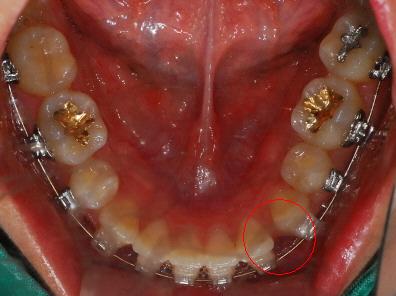

치과에 다녀왔습니다. 벌써 25번째 치아교정후기네요ㅎㅎㅎ 먼저 치아 사진을 보시면 아랫니에 공간이 살짝 생긴 것이 보이는 데요

<하악사진> 저는 처음에 왜 다시 벌어지지? 하고 걱정했는데 치과선생님께서 벌리는 것이 더 어렵다고 하셨어요~ 의도된 과정이었더라구요*^^* 이번달은 고무줄을 다시! 이용하여 윗니는 뒤로 아랫니는 앞으로 당겨주는 작업을 할거에요 그래서 고무줄은 위아래로 걸게 되었습니다~ 밥먹을 때 마다 뺏다 꼈다 해야 하는데 오랜만에 다시 고무줄끼니 정말....아프네요 맛잇는거 있어도 못먹고.. 옛날에 엄마가 치아가 많이 빠져서 딱딱한거 먹는 저랑 동생들 보면서 밥먹을때마다 부럽다고 하셨었는데 지금 제가 그러니 진짜 부럽고.. 엄마께 미안한 마음도 들고 그래요..ㅠㅠ